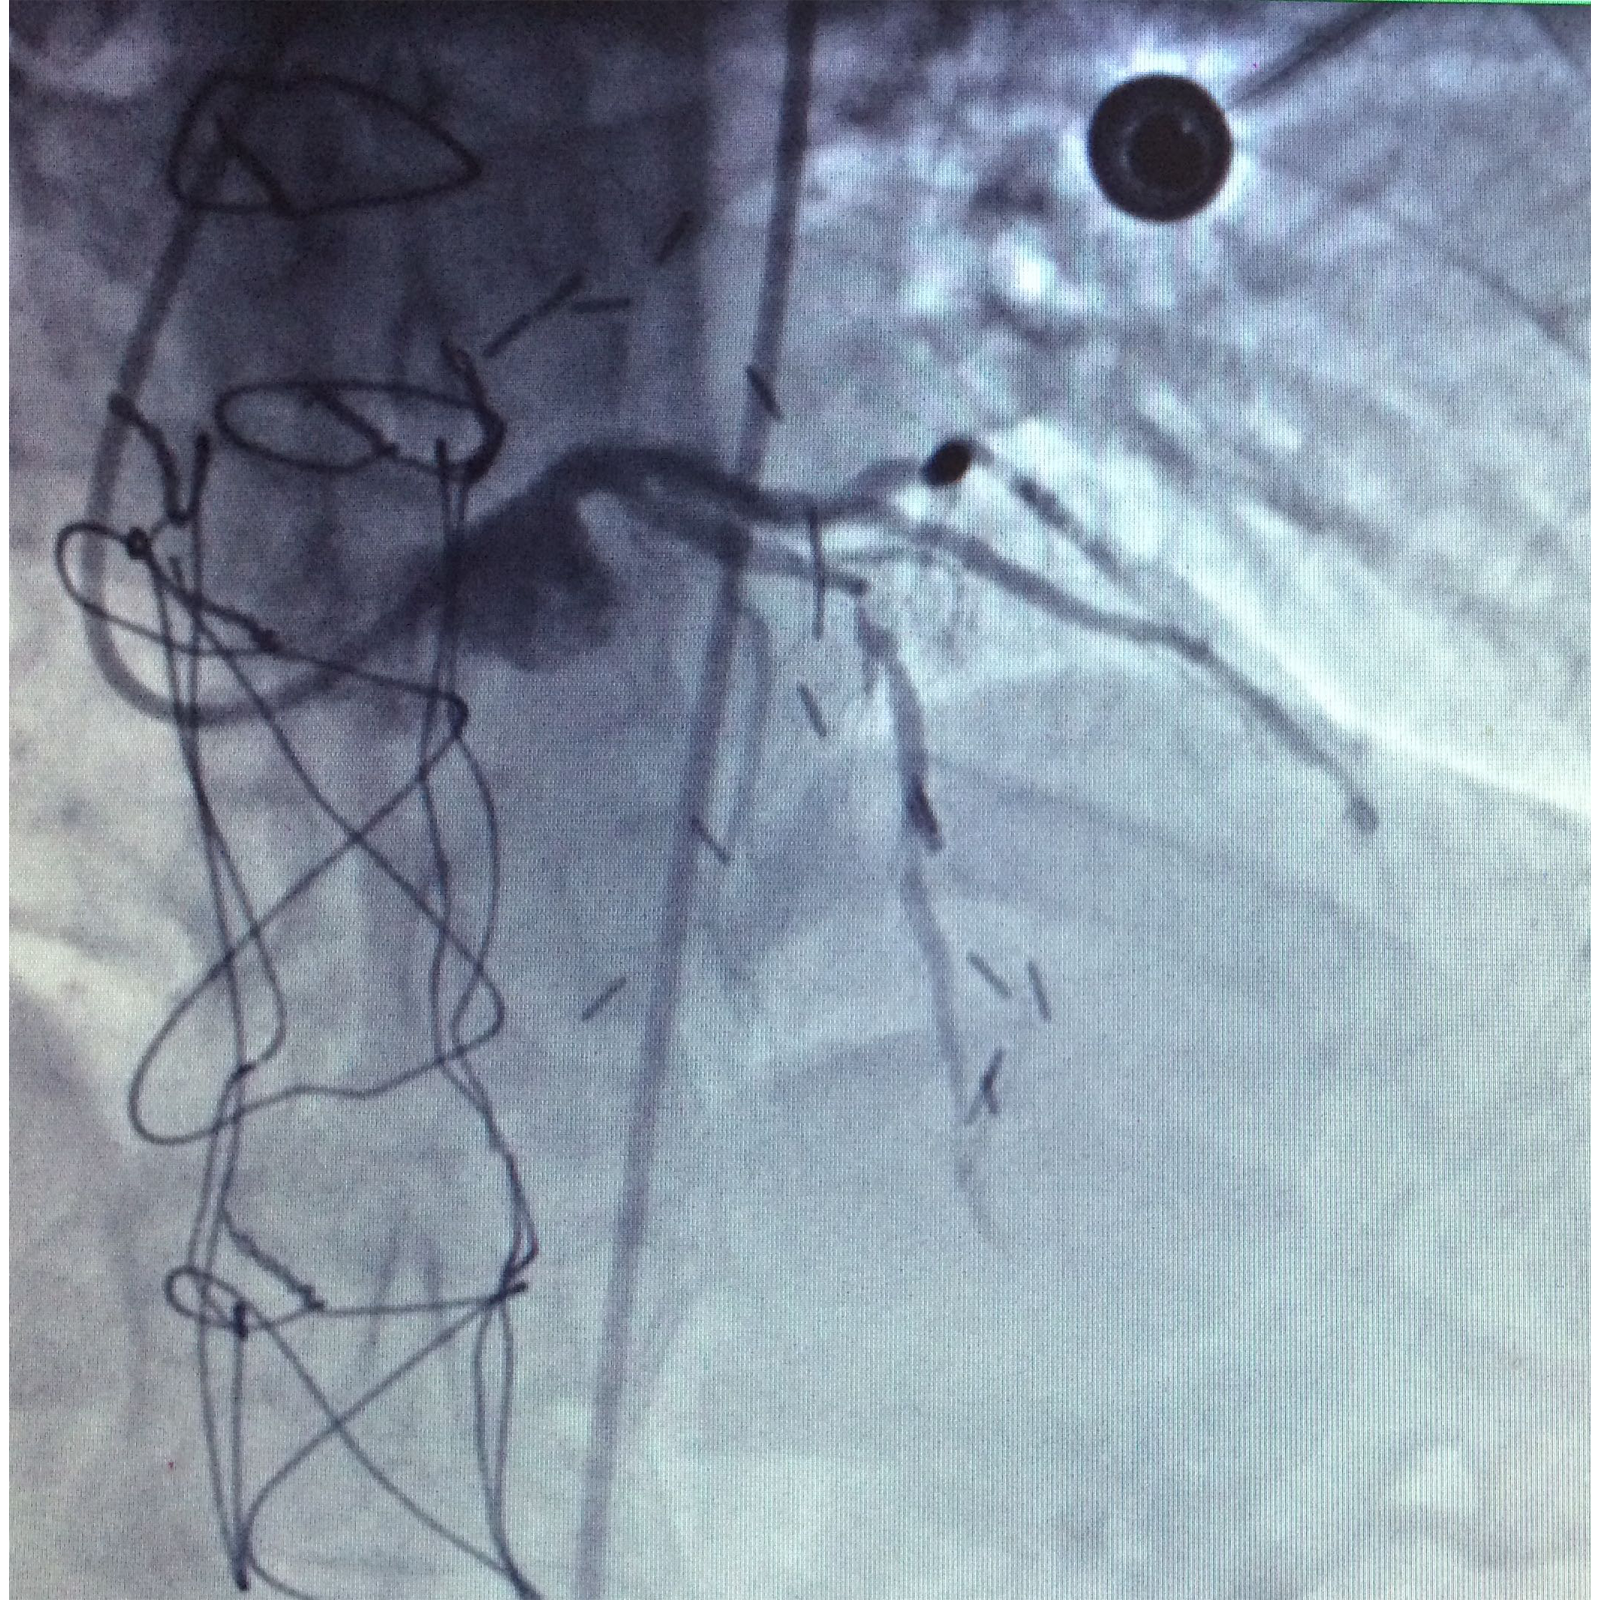

5. Right coronary artery with total occlusion at the proximal third (Figure 1-3).

Figure 1 Right coronary artery with total occlusion at the proximal third.

Figure 2 Right coronary artery with total occlusion at the proximal third.